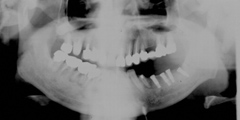

吉本歯科医院では、口内写真とパノラマレントゲンを撮影し、まずは顎の骨の状態まで詳しく確認しました。

写真(1)